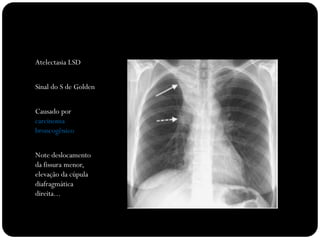

Atelectasia LSD

Sinal do S de Golden

Causado por

carcinoma

broncogênico

Note deslocamento

da fissura menor,

elevação da cúpula

diafragmática

direita...